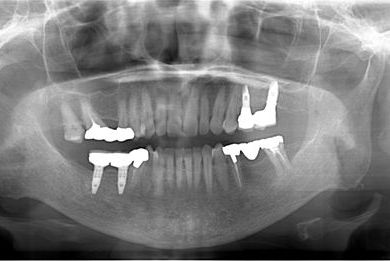

| 性別/年齢 | 女性 / 59歳 | ||||||||||||||||||||||||||||||||

| 主訴 | 奥歯がないので、インプラントか入れ歯の相談をしたい。 | ||||||||||||||||||||||||||||||||

| 治療方針 | 左上奥ソケットリフトにて上顎洞を拳上、骨再生法を行い、インプラント治療を可能にする。 | ||||||||||||||||||||||||||||||||

| 治療内容 | インプラント4本(GBR)、ハイブリッドセラミック4本 | ||||||||||||||||||||||||||||||||